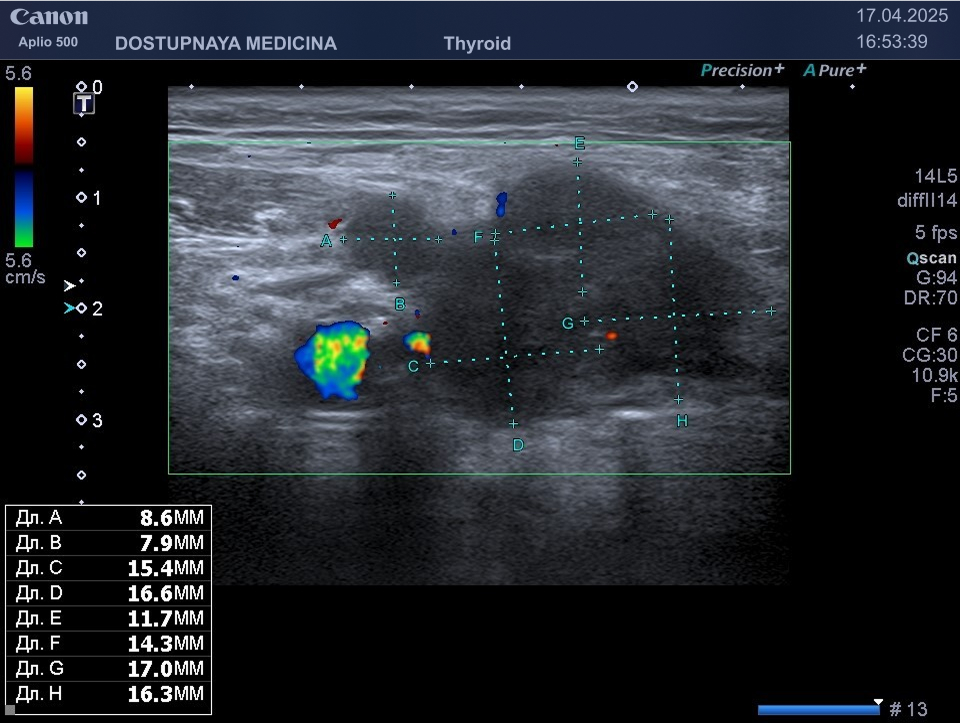

При ультразвуковом исследовании важно разобраться имеем мы дело с лимфаденопатией по воспалительному типу или с лимфаденопатией по пролиферативному типу. При лимфаденопатии по воспалительному типу сохраняется дифференцировка лимфоузла на слои, но корковый слой лимфатического узла утолщен, кровоток в лимфоузле хиларный (центральный), чаще всего отмечается усиление хиларного кровотока в режиме ЦДК, узел имеет овоидную форму и его горизонтальный размер всегда больше вертикального.

При лимфаденопатии по пролиферативному типу лимфоузел приобретает округлую форму и увеличивается в размерах, горизонтальный его размер становится равным вертикальному, кровоток перестаёт быть центральным и становится хаотичным, дифференцировка лимфоузла на слои отсутствует.

Лимфаденопатия по пролиферативному типу чаще встречается при лимфомах и при метастазах опухолей различных локализаций.